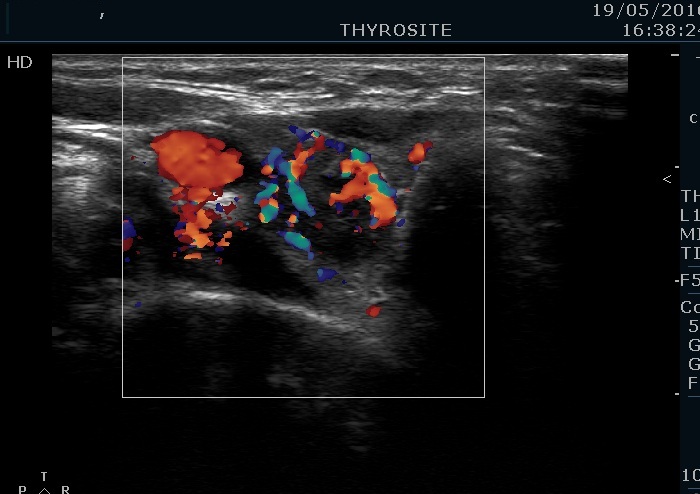

100 consecutive cases of papillary cancer - case 027 (ultrasonographic picture 6)

Lower part of the right lobe, transverse view, color Doppler mode. The nodule presents irregularly increased intranodular vascularization.